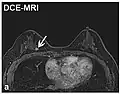

| Dynamic contrast enhanced | DCE | Measures changes over time in the shortening of the spin–lattice relaxation (T1) induced by a gadolinium contrast bolus.[90] | Faster Gd contrast uptake along with other features is suggestive of malignancy (pictured).[91] |